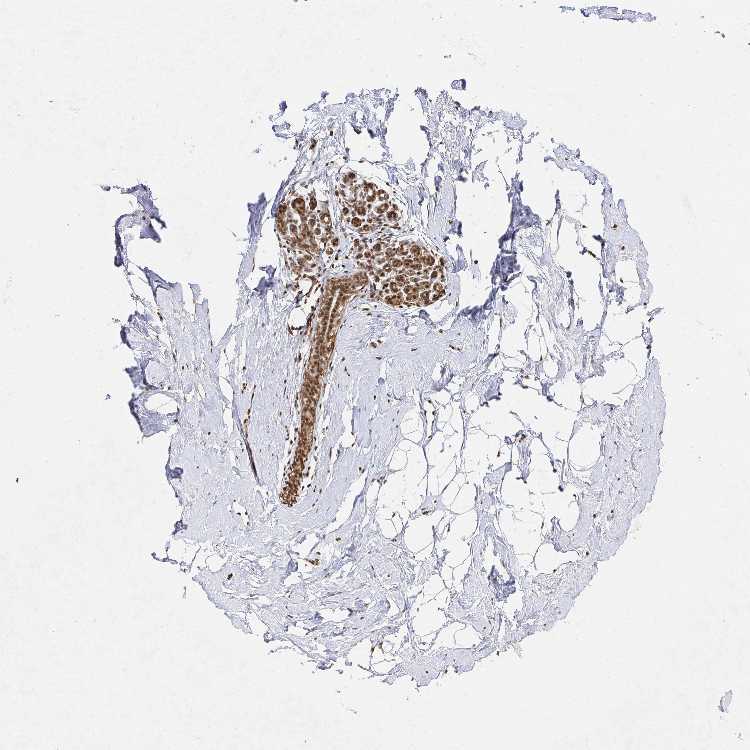

BREAST - Antibody stainingi

Antibody staining in the annotated cell types in the current human tissue is reported as not detected, low, medium, or high, based on conventional immunohistochemistry profiling in selected tissues. This score is based on the combination of the staining intensity and fraction of stained cells.

Each image is clickable and will lead to virtual microscopy that enables deeper exploration of all samples and also displays staining intensity scores, fraction scores and subcellular localization as well as patient and tissue information for each sample.

Antibody HPA056179Antibody HPA061345

Adipocytes Not detectedHigh

Glandular cells MediumHigh

Myoepithelial cells LowHigh